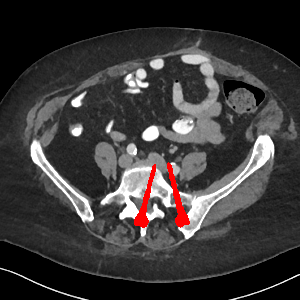

Visual comparison. As shown in Fig. 5, metallic implants such as spinal rods and hip prosthesis cause severe streaky artifacts and metal shadows, which obscure bone structures around them. cGan-CT cannot recover image intensity correctly for both cases. Sinogram domain or dual-domain methods perform much better than cGan-CT. LI, NMAR, and CNNMAR introduce strong secondary artifacts and distort the whole images. In NMAR images, there are fake bone structures around the metals, which is related to segmentation error in the prior image from strong metal artifacts. The segmentation error is also visible in NMAR sinogram. CNNMAR cannot restore the correct bone structures between rods in case 1. The tissues around the metals are over-smoothed in DuDoNet because LI sinogram and image are used as inputs, and the missing information cannot be inferred later. Our model retains more structural information than DuDoNet and generates anatomically more faithful artifact-reduced images.

Visual comparison. Fig. 7 shows two clinical CT images with metal artifacts. Case 1 is with moderate metal artifacts. cGan-CT does not suppress the artifacts completely and generates some fake details. LI, NMAR, CNN-MAR remove all the artifacts but introduce new streak artifacts, which is caused by the discontinuity in the corrected sinogram. DuDoNet outputs over-smoothed sinogram, which leads to blurred tissues close to the metal implants, such as muscle and bone. Only our model can provide realistic enhanced sinogram and remove the artifacts while retaining the structure of nearby tissues. Case 2 is very challenging as the rods bring strong metal shadows and bright artifacts around the vertebra. cGan-CT recovers the shape of vertebra but changes the overall image intensity. Other sinogram inpainting methods fail as the soft tissue and bone near the rods are heavily distorted. Our model removes part of the dark bands and reproduces correct anatomical structures around the rods.